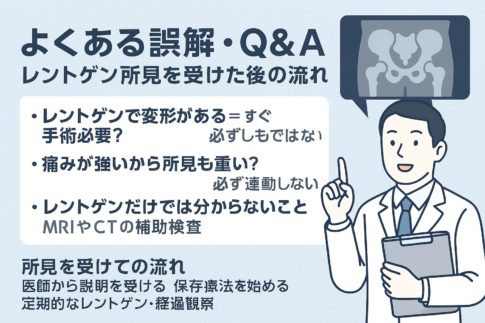

⑤ 痛みが続く場合・受診の目安(専門家の活用)

・次のような場合は医療機関へ

→ 痛みが消えない/しびれ・動かしにくい/赤く熱感がある等

・整形外科・リハビリの診療内容

→ 検査・治療の流れの目安(レントゲン・理学療法など)

⑤ 痛みが続く場合の考え方|来院を検討する目安

・「様子見」でよい痛みと、注意したいサインの違い

「セルフケアをしているけど、まだ違和感が残る…」

そんなとき、どこまで様子を見ていいのかは迷いやすいポイントです。

一般的には、

といった変化があれば、経過を見てもよい場合があると言われています。

一方で、

「数日〜1週間以上たっても変わらない」

「動かしていないのにズキズキする」

「可動域が明らかに狭くなった感じがある」

といった状態が続く場合は、体の中で別の要因が関係している可能性も考えられているそうです。

・運動を再開していいか迷ったときの考え方

「痛みはあるけど、運動してもいいのかな?」

この疑問も、よく聞かれます。

目安の一つとして、

「日常動作でも痛みが出る」

「フォームが崩れるほど気になる」

と感じる場合は、無理に再開しないほうがよいケースがあると言われています。

・来院時に伝えておきたいポイント

実際に来院を考える場合、

「何を伝えればいいかわからない」

と不安になる方も少なくありません。

その際は、

「いつから痛むか」

「どんな運動のあとに出たか」

「どの動きで一番つらいか」

といった点を整理しておくと、体の状態を共有しやすいと言われています。

第3章で行った

「場所・タイミング・動作」のセルフチェックが、ここで役立つケースも多いようです。

不安を一人で抱え込まず、体の状態を一緒に確認してもらうという考え方も大切だとされています。